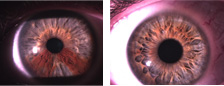

The iris resembles beautiful artwork when viewed close-up.